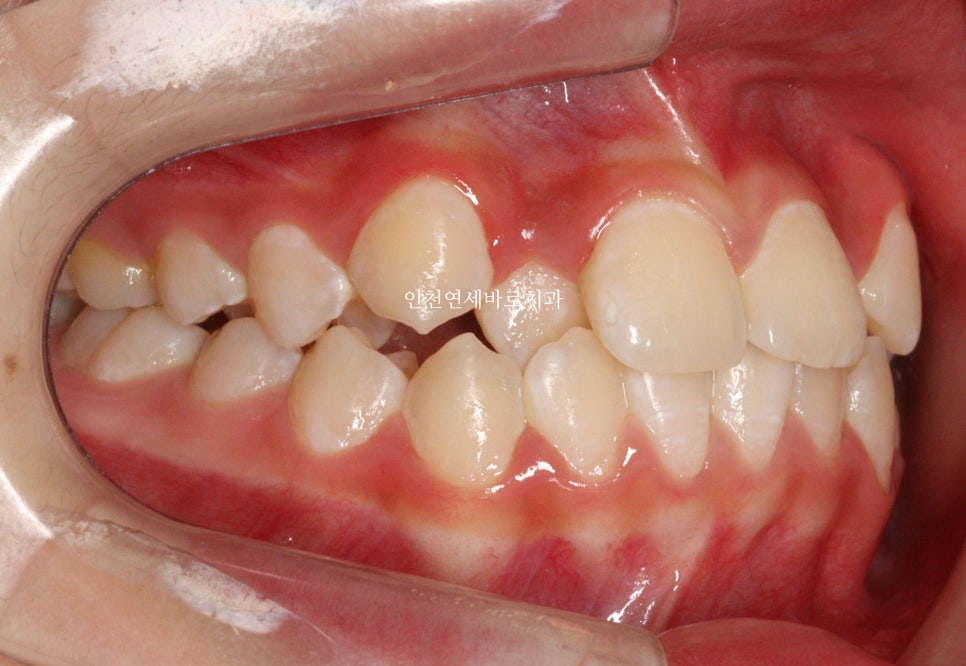

2023.4.18.에 처음 내원해서 23년6월초부터 치료를 시작한 아이입니다.

두번째 치아가 덧니로 있는 경우의 치료는 흔한 경우지만

생각보다 많은 노하우가 필요한 치료라고 생각합니다.

교정 치료 중에 화살표 최후방 치아가 맹출하여,

이 치아를 배열하는 과정에서 치료가 조금 더 길어지긴 했습니다